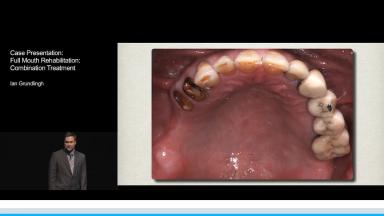

The rehabilitation of a partially dentate patient with a skeletal and dentate Class III relationship remains a challenge. The concerns raised by this patient were aesthetics and loss of function. He had a history of chronic sinusitis and was smoking at least ten cigarettes per day. The intra oral examination revealed loss of posterior teeth due to caries, which resulted in severe bone loss, loss of occlusal vertical dimension and compromising the anterior aesthetics.